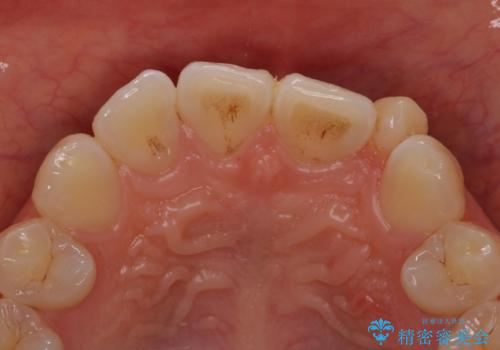

- 左上の前歯が生まれつき小さく、前に飛び出していました。

矯正治療で引っ込めてから、形を左右対称に整えるセラミック治療を行いました。